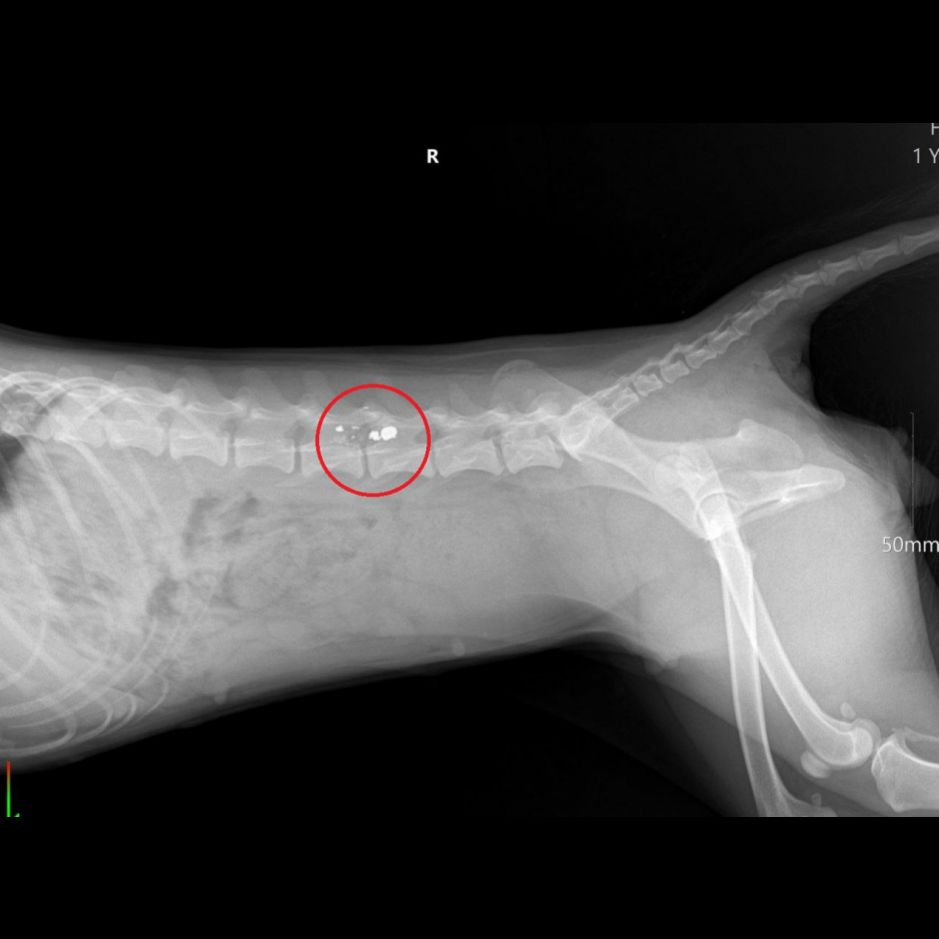

Хозяева доставили собаку в ветеринарную клинику. Врачи диагностировали травмы, которые привели к параличу задних лап.